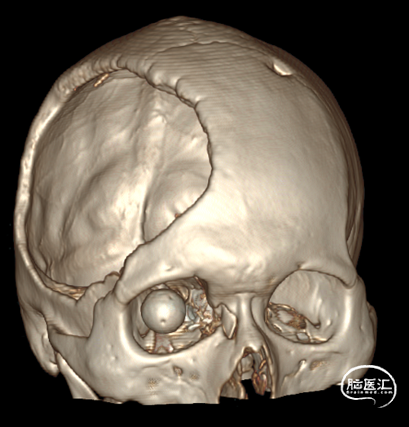

术后即时影像

血管造影影像